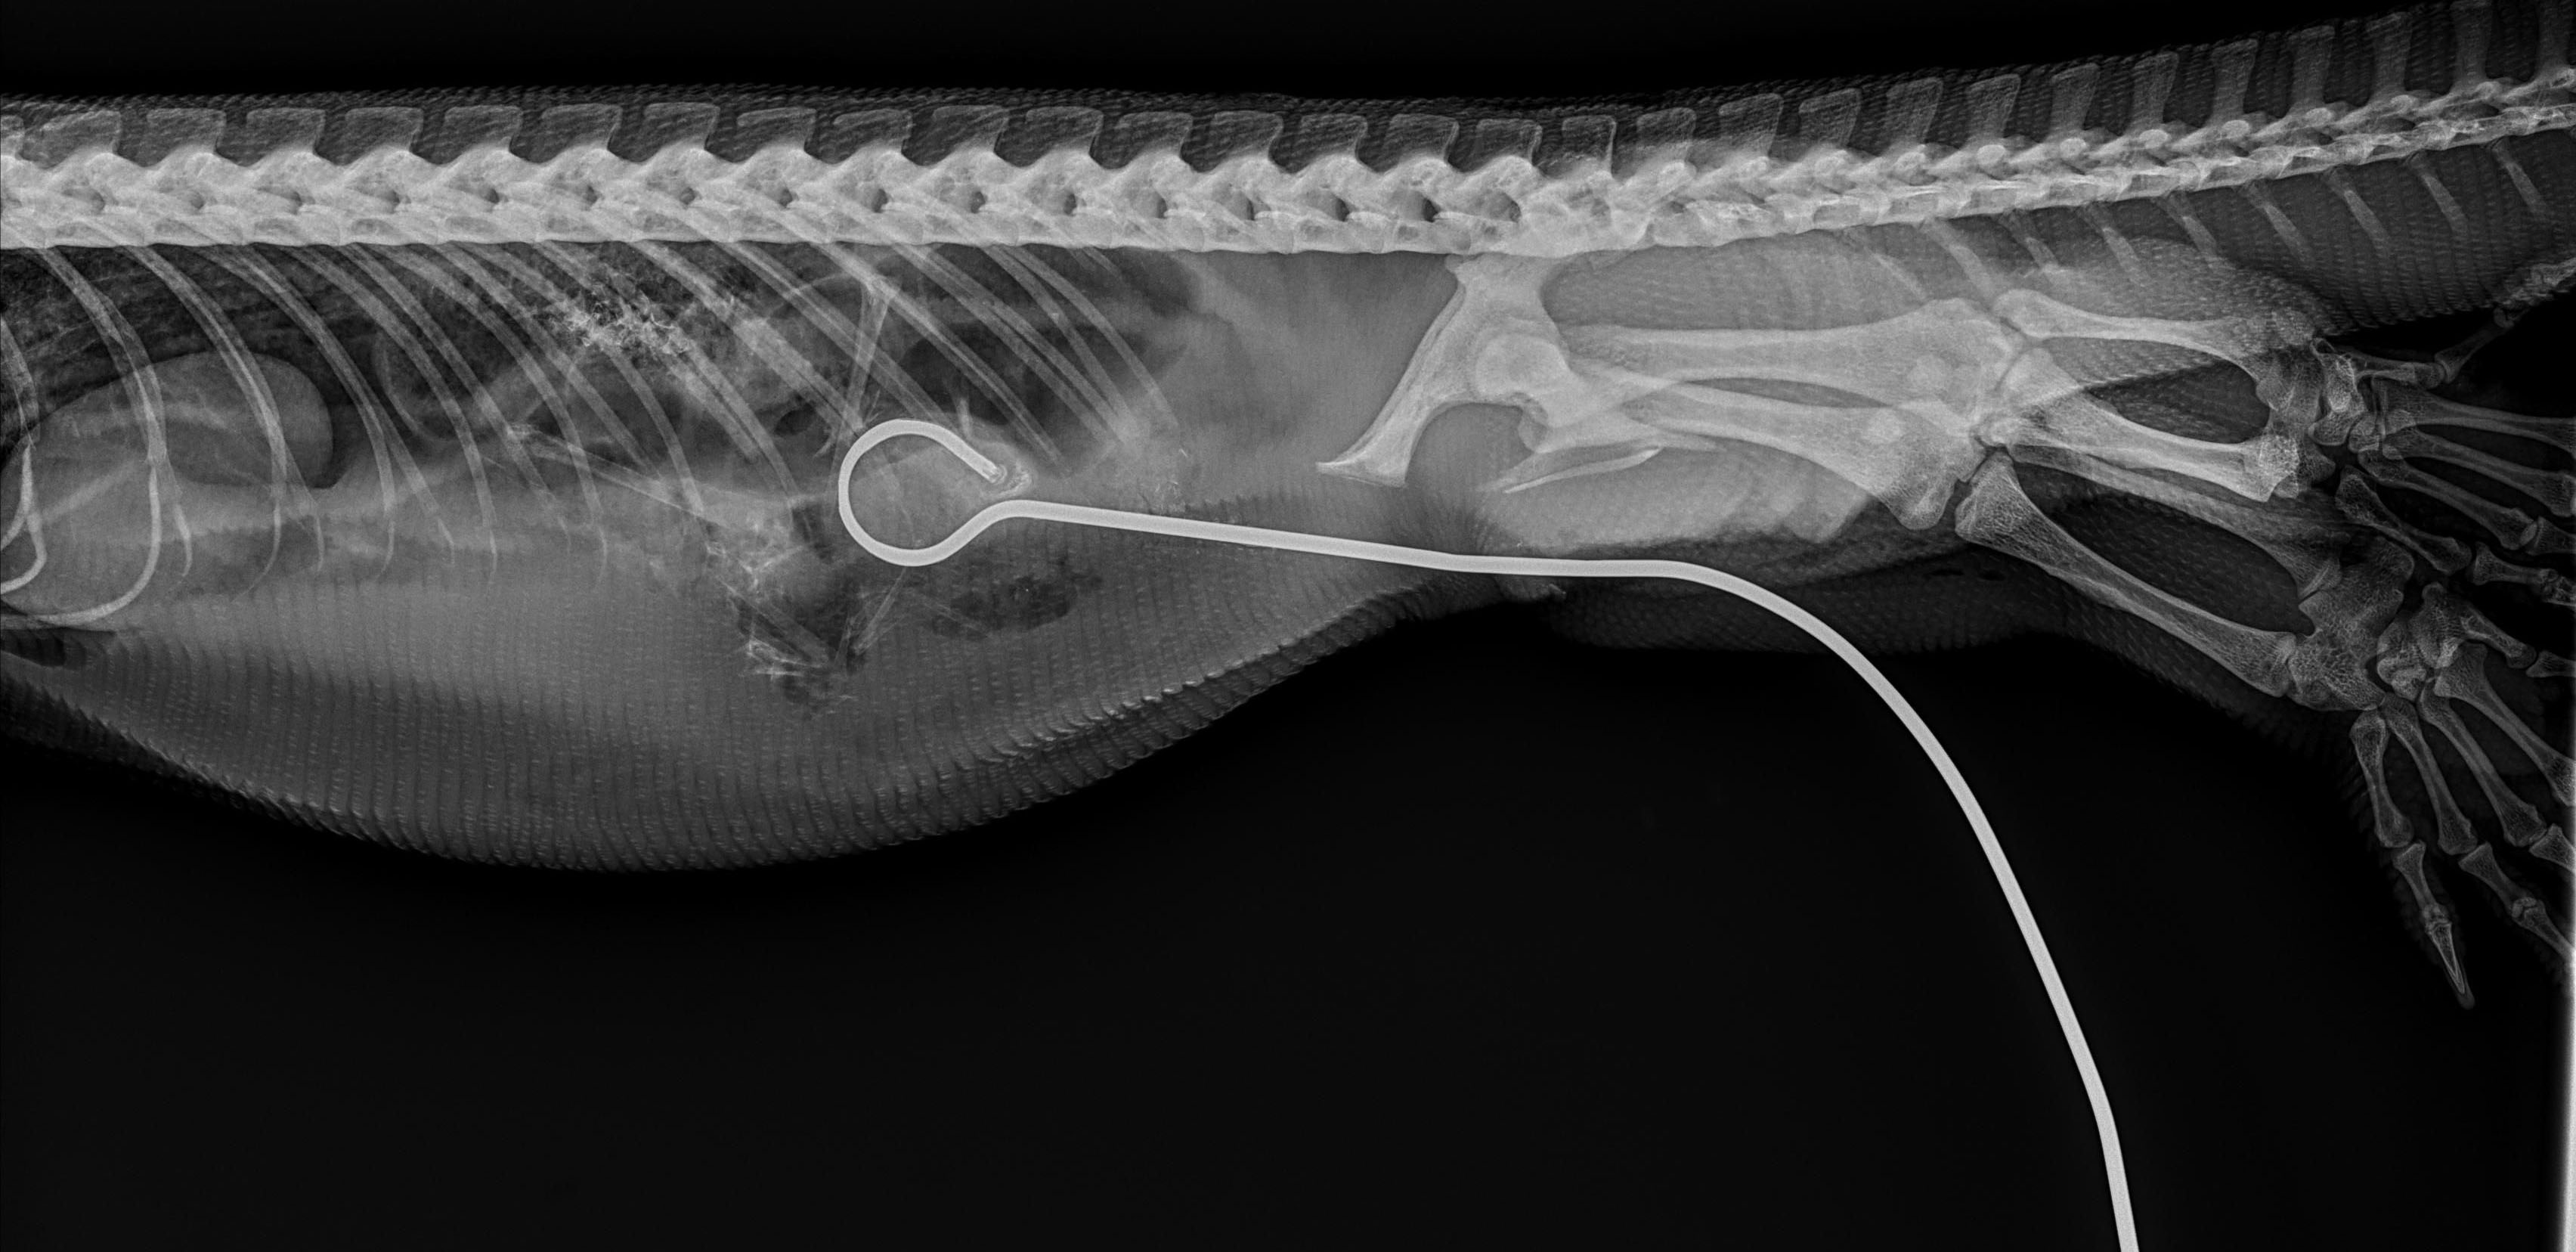

Following admission to the Wildlife Intensive Care ward at Taronga the animal underwent a veterinary assessment by Taronga Vet, Dr. Gabrielle Tobias. Gabrielle performed x-rays to ascertain the best course of action based on where the skewer was sitting.

‘’I was disappointed to see that the skewer had a ring on the end which would make removal more difficult. I was unable to differentiate where the end of the skewer was seated within his body cavity.’’ said Gabrielle.

Dr. Gabrielle with the assistance of fellow Taronga Veterinarians, Taronga Vet Nurses and a Veterinarian Intern performed a gruelling 4-hour surgery to remove and repair the damage caused by the ingested skewer.